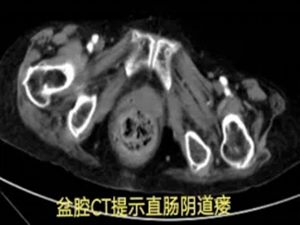

在积极止血过程中,团队发现出血并非单纯的直肠肛门问题,怀疑可能合并阴道瘘。初步处理后,患者被转入胃肠甲状腺外科进一步诊治,最终确诊为直肠阴道瘘并局部感染出血。

然而,真正的挑战才刚刚开始:患者20多年前曾接受直肠肿瘤手术,此次手术方案的制定难度陡增。高龄、既往直肠癌手术史、阴道瘘感染、凶猛的出血——其中任何一项单独出现,都已属高危;此刻,却全部叠加在一起。

杨战锋主任建议启动"疑难病例云平台",共商手术预案。经北上广深多位专家线上会诊,最终探讨出最佳治疗方案。手术顺利完成后,患者平安度过危险期。